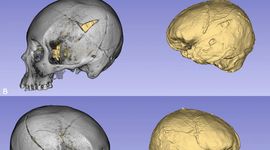

Scanând mumiile preistorice din deșertul Atacama, cercetătorii au descoperit că un individ Chinchorro avea, în medie, un creier cu aproximativ 12% mai mic decât cel al unui chilian modern, un indiciu al malnutriției din copilărie și al condițiilor precare de viață.

Pentru a afla mai multe despre starea de sănătate a acestor locuitori preistorici ai deșertului, autorii studiului au realizat tomografii computerizate (CT) pe 68 de capete mumificate ale culturii Chinchorro și le-au comparat cu nouă indivizi agricultori antici din aceeași regiune, precum și cu 83 de chilieni contemporani. În ansamblu, au constatat că volumul intracranian (ICV), un indicator al mărimii creierului, era în medie de 1.321,26 centimetri cubi la mumiile Chinchorro, 1.336,57 centimetri cubi la agricultorii prehispanici și 1.481,22 centimetri cubi la populația actuală.

Așadar, deși dimensiunea creierului nu pare să se fi schimbat prea mult după trecerea de la stilul de viață de vânător-culegător la cel sedentar, epoca modernă pare să fi declanșat o creștere masivă a ICV. Comparând cele mai vechi mumii cu cohorta modernă, cercetătorii au observat o expansiune cerebrală de 12,05%.